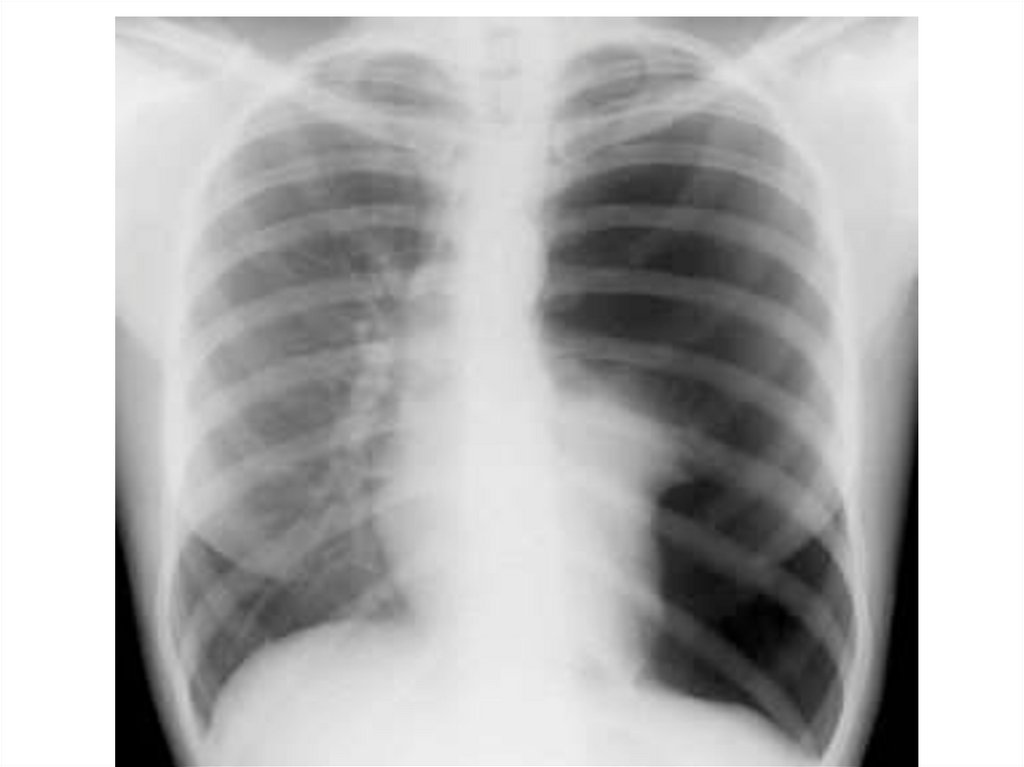

Негативное изображение

• Затенение – светлое

• Просветление - тёмное